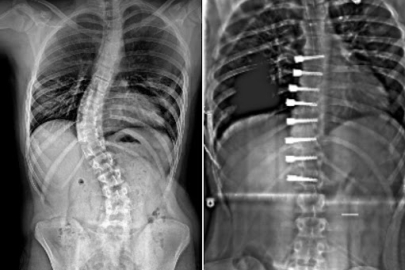

Fiziksel Tıp ve Rehabilitasyon Uzmanı Uzm. Dr. Emre Latifoğlu, dijital çağın beraberinde getirdiği tehlikelere dikkat çekerek, çocuklarda omurga sağlığı sorunlarında gözle görülür bir artış yaşandığını belirtti. Uzaktan eğitim ve uzun süreli ekran maruziyetinin, çocuklarda "telefon boynu" ve "kambur oturuş" gibi duruş bozukluklarını tetiklediğini ifade eden Dr. Latifoğlu, büyüme çağındaki esnek omurganın yanlış pozisyonlarda uzun süre kalması sonucunda kalıcı eğrilikler (skolyoz) oluşabileceği uyarısında bulundu. SİNSİCE İLERLİYOR Skolyozun genellikle sinsi ilerleyen bir rahatsızlık olduğunu vurgulayan Uzm. Dr. Emre Latifoğlu, ailelerin çocuklarını yakından gözlemlemesi gerektiğini söyledi. Dr. Latifoğlu, aileleri şu kritik belirtilere karşı uyardı: Omuzlardan birinin diğerinden yüksek durması, kalça seviyesinde asimetri, giysilerin sürekli bir tarafa toplanması ve özellikle öne eğilme sırasında sırtın bir tarafının kabarık görünmesi. Uzman, bu belirtilerin fark edilmesi durumunda, skolyoz grafisiyle erken tanı konulabileceğini ve erken teşhisin tedavide büyük önem taşıdığını vurguladı. HASTALIĞIN İLERLEMESİNİ ÖNLEMEDE NE ETKİLİ? Erken tanı konulan skolyoz vakalarında tedavinin başarı oranının yüksek olduğunu belirten Uzm. Dr. Emre Latifoğlu, özellikle büyüme döneminde tespit edilen eğriliklerin kontrol altına alınabildiğini kaydetti. Dr. Latifoğlu, "Özel egzersizler ve korselerle eğrilik ilerlemeden kontrol altına alınabiliyor" diyerek tedavi yöntemlerine değindi. Fiziksel tıp ve rehabilitasyon uzmanları tarafından kişiye özel hazırlanan programların, hem duruş bozukluklarını düzeltmede hem de skolyozun ilerlemesini önlemede kritik bir rol oynadığını ekledi.

Fine Fizyoterapi Diyet ve Sağlıklı Yaşam Merkezi’nin kurucu ortaklarından Fizyoterapist Neslihan Söyler, skolyoz ve tedavisinde kullanılan Schroth terapi yöntemi hakkında Bursa Hayat’a detaylı bilgiler verdi. Fizyoterapist Neslihan Söyler, skolyozun, omurganın yana doğru veya kendi ekseni etrafında anormal eğrilmesi sonucu ortaya çıkan bir rahatsızlık olduğunu dile getirdi. Söyler, bu durumun her yaş grubunda görülebildiğini vurgulayarak, en sık 10-18 yaş arasındaki çocukların ergenlik döneminde rastlandığını belirtti. Bu dönemde büyümenin hızlı olması nedeniyle skolyozun daha hızlı ilerleyebileceği uyarısında bulundu. ERKEN TEŞHİSİN ÖNEMİ Neslihan Söyler, skolyoz tedavisinde erken teşhisin kritik önem taşıdığını vurgulayarak, fiziksel belirtiler arasında omuz seviyelerindeki eşitsizlik, kürek kemiklerinden birinin diğerine göre belirgin çıkıklığı ve kalça seviyesindeki dengesizliğin yer aldığını belirtti. Söyler, erken teşhis sayesinde omurga eğriliğinin ilerlemesinin önüne geçilebileceğini ifade etti. SCHROTH TERAPİ YÖNTEMİ NEDİR? Söyler, Schroth terapi yönteminin skolyoz tedavisinde kullanılan üç boyutlu egzersizlerden oluşan kişiye özel bir terapi programı olduğunu belirtti. Bu yöntemin diğer egzersiz yöntemlerinden farklı olarak tamamen bireyin omurga yapısına göre planlandığını vurguladı. Söyler, yöntemin temel unsurlarının postürel düzeltme, rotasyonel solunum teknikleri ve kas dengesini sağlamaya yönelik egzersizler olduğunu ifade etti. TERAPİ SÜRECİ NASIL İŞLİYOR? Söyler, skolyoz tedavisinde her bireyde farklı bir süreç izlediğine dikkat çekerek, “Tedavi süresi, hastanın yaşına, eğriliğin derecesine ve terapiye olan uyumuna göre değişiklik gösterebiliyor. Bazı bireyler için 6 ay yeterli olurken, bazıları için bir yıl boyunca düzenli takip ve egzersizler gerekebiliyor.” dedi. SKOLYOZUN FARK EDİLMESİ VE AİLELERİN ROLÜ Neslihan Söyler, skolyozun özellikle küçük açılarda fark edilmesinin zor olabileceğini, bu yüzden ailelerin çocuklarının omuz seviyelerini, kürek kemiklerini ve bel-kalça çizgilerini düzenli olarak gözlemlemeleri gerektiğini vurguladı. Ayrıca skolyozun postür bozukluğu ile karıştırıldığını belirten Söyler, profesyonel bir değerlendirme yapılmadan egzersizlere başlanmaması gerektiğinin altını çizdi. Skolyoz tedavisinde Schroth terapinin cerrahi müdahale dışındaki en etkili yöntemlerden biri olduğunu söyledi. İnsanların, YouTube gibi platformlarda genel egzersiz videoları izleyerek kendi başına uygulama yapmasının yanlış olduğunu belirten Söyler, her bireyin omurga yapısının farklı olduğu için kişiye özel bir tedavi programı uygulanması gerektiğini vurguladı. Ebeveynlere çocuklarını spora yönlendirmelerini öneren Söyler, sporun kas kuvvetini artırarak omurgayı desteklediğini belirtti. Skolyoz hakkında bilinçlenmenin arttığını dile getiren Neslihan Söyler, erken teşhis ve düzenli takip ile başarılı sonuçlar alınabileceğini ifade etti.